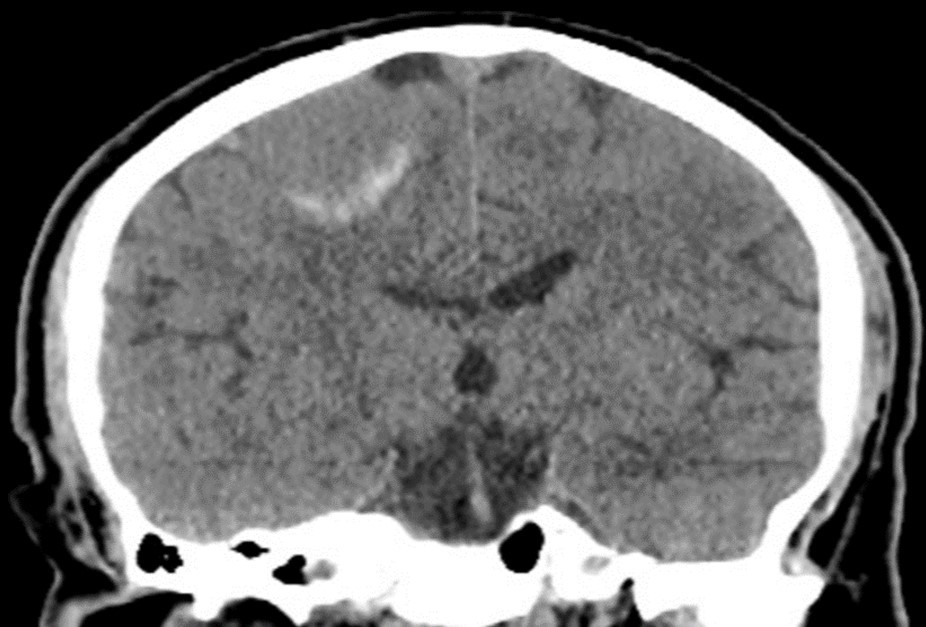

Treatment planning for LINAC-based radiosurgery has been performed by ERGO ++ (CMS, Elekta, UK) radiosurgery planning system. Optimal target coverage and normal tissue sparing has been achieved by using a single 360-degree arc, double 360-degree arcs, or five 180-degree arcs in radiosurgery planning. Synergy (Elekta, UK) LINAC available at our department has been used in delivery of treatment. Delineation of the target volume on planning CT and MR images has been optimized by selecting the appropriate windows and levels for radiosurgery planning. Sagittal and coronal images have been used in addition to the axial planning CT images to achieve accurate contouring of target volume and critical structures. Arc Modulation Optimization Algorithm (AMOA) has been utilized for optimization of target volume coverage and critical organ sparing. Figure 1 shows coronal CT image of a patient with atypical meningioma, and Figure 2 shows the corresponding coronal MR image of the same patient with atypical meningioma.

Figure 1.Coronal CT image of a patient with atypical meningioma